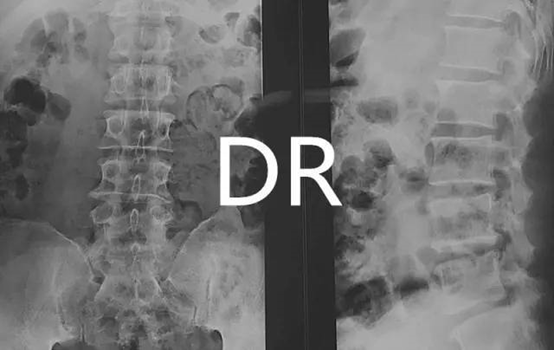

在临床工作中很多患者会存在这样的疑问:为什么我照腰椎要躺着?那我肚子不是把腰挡上了吗?还能照到腰吗?那么就让我们来讲解一下吧:为什么拍腰部X光片要躺着而不是趴着?

主要是因为相较于趴着,躺着能够更清晰地观察骨骼结构,有助于发现病变。

X光是一种影像学检查,也称为X线检查,是临床上常见的检查方法之一,可以用于检查骨骼的形态、位置、大小等情况。X光检查的原理是利用X射线对人体进行照射,由位于摄影床上的探测器接收透过人体组织的X线,经过数模转化输入计算机,最后形成2维的影像。在进行X线检查时,患者仰卧于摄影床上可以减小投照部位到探测器的距离,再配合上X线极强的穿透力,能够极大的减少放大失真度,并且仰卧位也可以增加患者的稳定性,从而使检查结果更加清晰地显示出骨骼和关节的形态和结构,有助于发现病变。